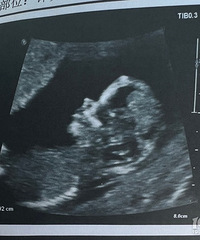

预产期:2022.10.2建卡医院:温岭妇幼保健院产检医院:温岭妇幼保健院胎宝宝小名:安安生产医院:暂定温岭妇幼保健院B超照片/孕期相关照片一张